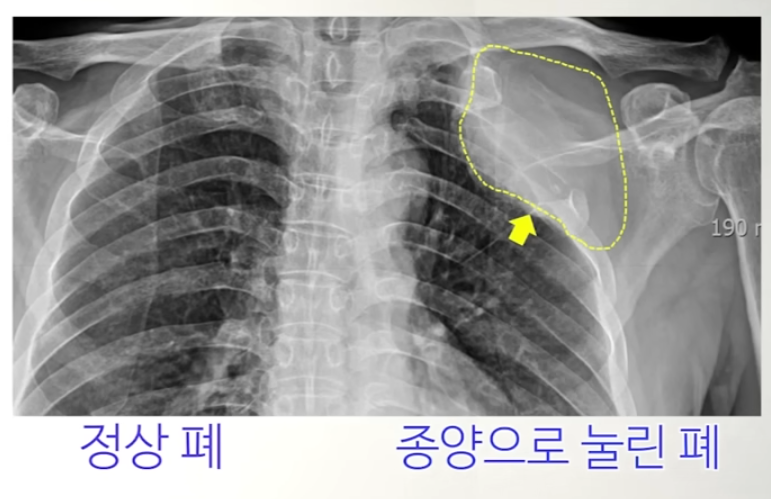

1. 종양의 성장

폐암이 진행되면 종양이 점차 커지면서 폐 주변의 조직과 구조물에 압력을 가하게 됩니다. 폐에는 여러 중요한 구조물이 밀집해 있기 때문에, 종양이 성장하면서 주변 신경이나 혈관, 뼈 등을 압박하거나 침범할 수 있습니다. 이때, 특히 상완 신경총(brachial plexus)이라는 신경 다발이 압박을 받으면 어깨에 통증이 발생할 수 있습니다. 상완 신경총은 팔과 어깨를 포함한 상체의 감각과 운동을 담당하는 신경망이기 때문에, 이 신경이 압박되면 어깨뿐만 아니라 팔과 손에도 통증이나 저림, 마비가 동반될 수 있습니다.